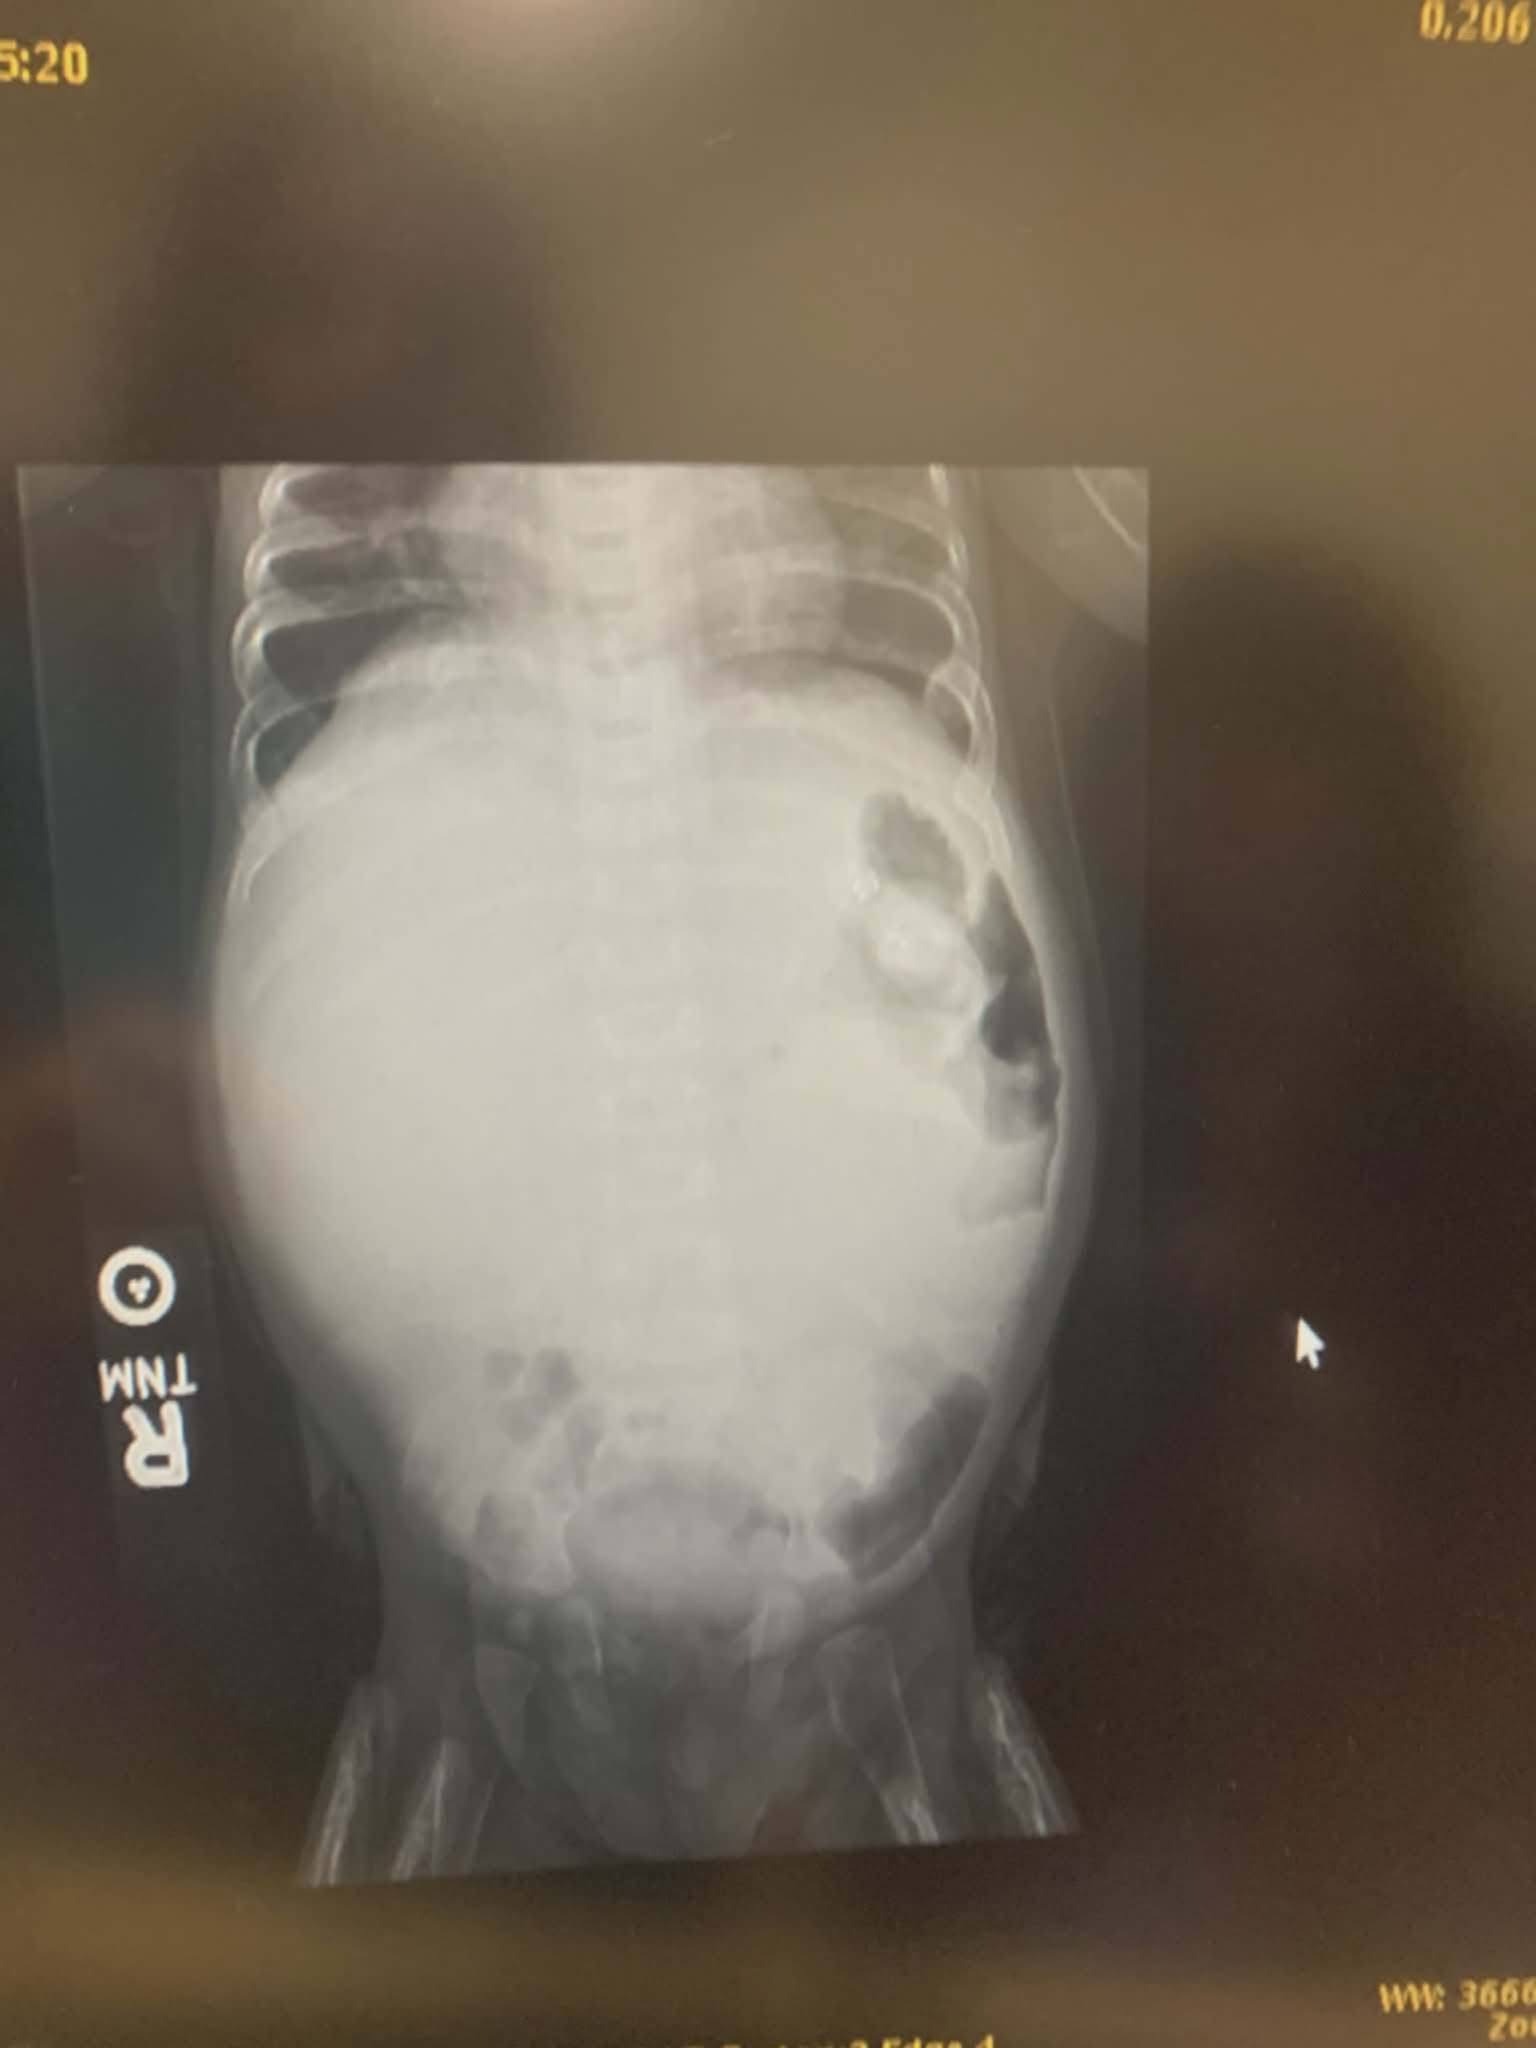

On March 30th, 2026, Tristan was taken to the hospital after his stomach was enlarged and uncomfortable. After multiple tests, including bloodwork, an ultrasound, and an MRI, doctors discovered a tumor on his liver that has been identified as cancerous. A biopsy is going to be done and then his medical team will determine the next steps in his treatment-such as chemo therapy and surgery.